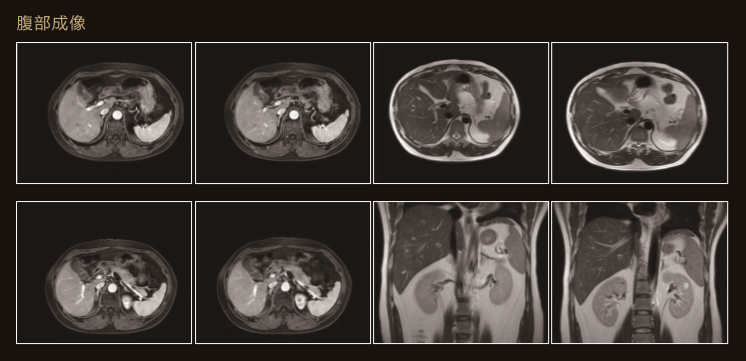

臨 床 圖 集

Apsaras飛天保持高操作性能的同時進一步追求臨床價值

Apsaras飛天不僅采用極高均勻度的磁體系統,還配備了高階勻場系統可大範圍的高階磁場校正,以獲得具有臨床價值的圖像。

Apsaras飛天在保持以往使用便捷的前提下,應用程序支持更全面的臨床應用和發展。

T2值得變化可以通過彩色圖表示從而達到更好的組織變性的目測性